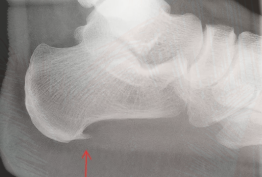

皆さん、足の底の痛みに悩まされたことはありませんか? 今日はその中でも頻度の多い、足底筋膜炎についてご紹介します。 ![]() 足底筋膜炎は、足底筋踵骨付着部の年齢変化による微小断裂です。 40歳代以降の男性に多く、朝の第1歩から踵の内方に激痛が出ますが、数分でなくなります。 これは変性してもろくなった付着部が、古くなったゴム管のように細かく断裂を起こし、一晩寝ると断裂部はかさぶたのように癒合しますが、十分な強度には回復しないので、翌朝には再び断裂するためです。 数カ月にわたって繰り返しますが、そのうちに元の長さに戻らなくなって、ついには踏み返しても断裂しなくなって、痛みは自然と消失するといわれています。 ![]() 治療としては足底板や湿布や塗り薬、症状が強い場合にはステロイドの注射を行うこともあります。大半が自然軽快しますので、ストレッチにも励むようにして下さい。 もし足の痛みがあるようなら、いつでも「うちのう整形外科」を受診されて下さい。 うちのう整形外科 錦町 院長 矢坂治彦 日本整形外科学会専門医 |